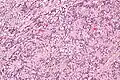

High mag.

IPMs are diagnosed by examination of the tissue by a pathologist. They have a rim of peripheral lymphoid tissue (remnant of a lymph node) and consist of spindle cells with nuclear palisading. Red blood cell extravasation is common and blood vessels surrounded by collagen with (fine) peripheral spokes (amianthoid fibers) are usually seen.[2]

Immunostains for smooth muscle actin and cyclin D1 are characteristically positive. The main histologic differential diagnosis is schwannoma.